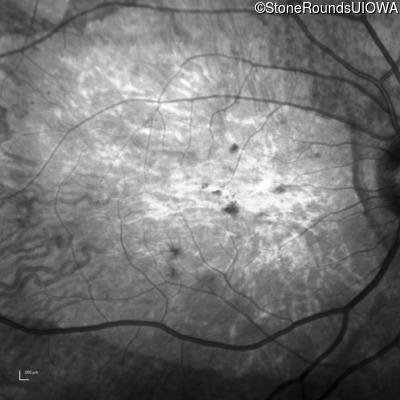

Infrared Fundus Photograph - Right - 20/250 sc

Exemplar